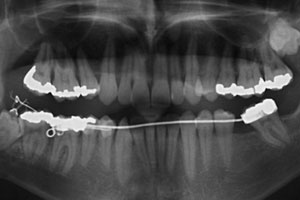

After 7 months of orthodontic extrusion, radiography showed a significant reduction in the size of the cystic cavity and the apposition of new bone on the distal surface of the second molar (Fig. 5). As the roots of the impacted tooth were now farther from the mandibular canal, it was decided to deactivate the cantilever and extract the third molar after a 3-month retention phase. During surgery, the cyst was also completely removed. Tooth extraction was simple, and healing was uneventful with no neurologic damage. At 2 years follow up, probing pocket depth was 2 mm on the lingual side and 3 mm on the buccal side of the distal root surface of the second molar; a large amount of crestal bone apposition was detected on the radiograph and crestal bone loss was now only 2 mm — an 87.5% reduction in the extent of the bone defect compared with the initial observation (Fig. 6).

Figure 5: After 7 months of orthodontic extrusion, panoramic radiography shows a reduction of the cystic cavity and apposition of bone on the distal surface of the right mandibular second molar.

After 7 months of orthodontic extrusion followed by a 3-month retention phase to ensure adequate bone maturation,11 a significant reduction in the cystic cavity had occurred as well as new bone apposition on the distal surface of the second molar. At a 2-year follow-up appointment, clinical and radiographic examination confirmed that only a minimal bone defect remained on the distal surface of the second molar (Fig. 6). Thus, combining marsupialization with orthodontic extraction enhanced bone apposition, decreasing the risk of periodontal breakdown at the distal surface of the second molar and increasing the resistance of the mandible. The latter was of utmost importance as the patient was a windsurfing instructor and, thus, prone to pathologic fracture.